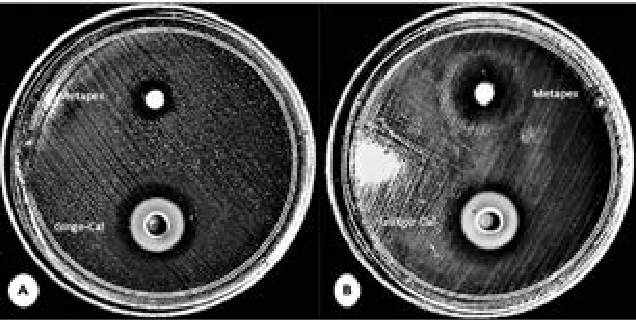

Manuka Oil Vs. Oral Pathogens: An Overview

RE Carlson and JA von Fraunhofer. 21(12): 148-154.